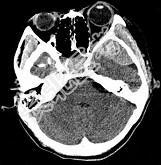

- 单项选择题男性,25岁, 外伤后行CT检查,最可能的诊断为 ( )

A、左顶枕部硬膜下血肿

B、左顶枕部硬膜外血肿

C、左顶枕叶出血

D、脑挫裂伤

E、脑膜瘤